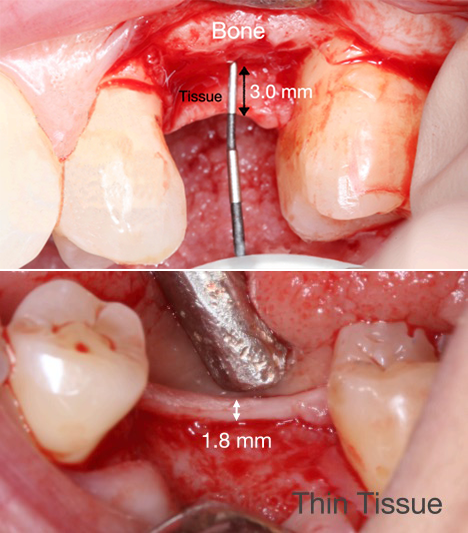

crestal, but this is a placement relative to the level of the implant in the bone. It is interesting to question the bone position as the point chosen for implant placement, as often the bone is not level and is very scalloped. Figure 4 shows the original vertical tissue to be at 1.8 mm.

Fig 4. Vertical soft-tissue thickness plays an important role in the etiology of crestal bone loss.

Figure 4